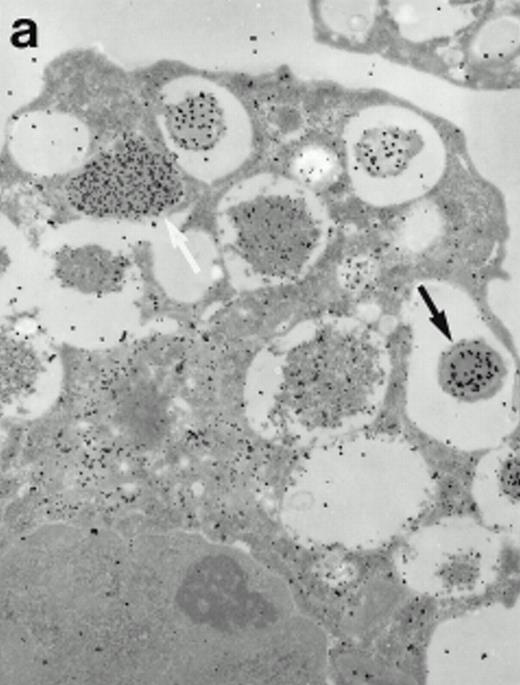

Morphologic analyses of both mature eosinophils and day-24 IL-5–induced UCC by immunoelectron microscopy were performed with proMBP-specific monoclonal antibody (J163-15E10) and with polyclonal antibody to MBP (rabbit #14). No proMBP staining was observed in peripheral blood eosinophils (Fig 6a); in contrast, MBP was localized specifically to the granule crystalline core (Fig 6b). Day-24 IL-5–induced UCC showed marked proMBP labeling of large uncondensed granules and minimal labeling of small condensed granules (Fig 6c); remarkably, proMBP was often seen as a ring around what appeared to be a granule in the process of condensing (black arrow). MBP labeling was confined primarily to condensing granules (Fig6d). Figure 7 shows results from double immunogold labeling of both proMBP (small gold) and MBP (large gold). ProMBP was concentrated in large uncondensed granules, and MBP was concentrated in condensed granules. Some granules (black arrow in Fig7b) contained labeling for MBP (primarily in the center) and proMBP (at the periphery). Controls using either normal mouse immunoglobulin or normal rabbit immunoglobulin as the primary label were negative (results not shown).

Localization of proMBP and MBP by immunoelectron microscopy. (a) A peripheral blood eosinophil labeled with anti-proMBP J163-15E10. Note the absence of specific labeling. (b) A peripheral blood eosinophil labeled with rabbit anti-MBP. Note that MBP is specifically localized to the granule crystalline core (black arrows). (c) Day-24 IL-5–induced UCC labeled with anti-proMBP. The black arrow shows localization of proMBP predominantly to the periphery of a condensing granule; very little proMBP is present in the interior of that granule. The white arrow points to a condensed granule, which lacks proMBP label. Also, note the presence of a large uncondensed granule densely labeled with proMBP proximal to the nucleus (open white arrowhead). (d) Day-24 IL-5–induced UCC labeled with anti-MBP. MBP is localized primarily to the interior of condensing granules (black arrows). (a, c, and d) Original magnification ×11,000; (b) ×15,000.